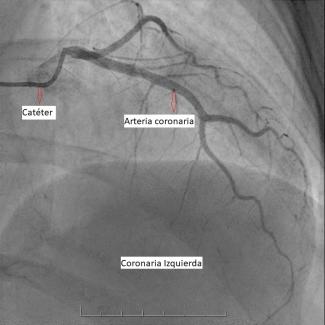

La sala donde te realizarán el estudio se encuentra a baja temperatura. Este procedimiento se efectúa con anestesia local y comienza con la introducción de un catéter por punción en una de las arterias de la muñeca o la ingle, de acuerdo a las características de cada persona.

Este catéter llega hasta las arterias coronarias y una vez allí se inyecta una sustancia de contraste, que permite visualizarlas y verificar si hay obstrucciones.